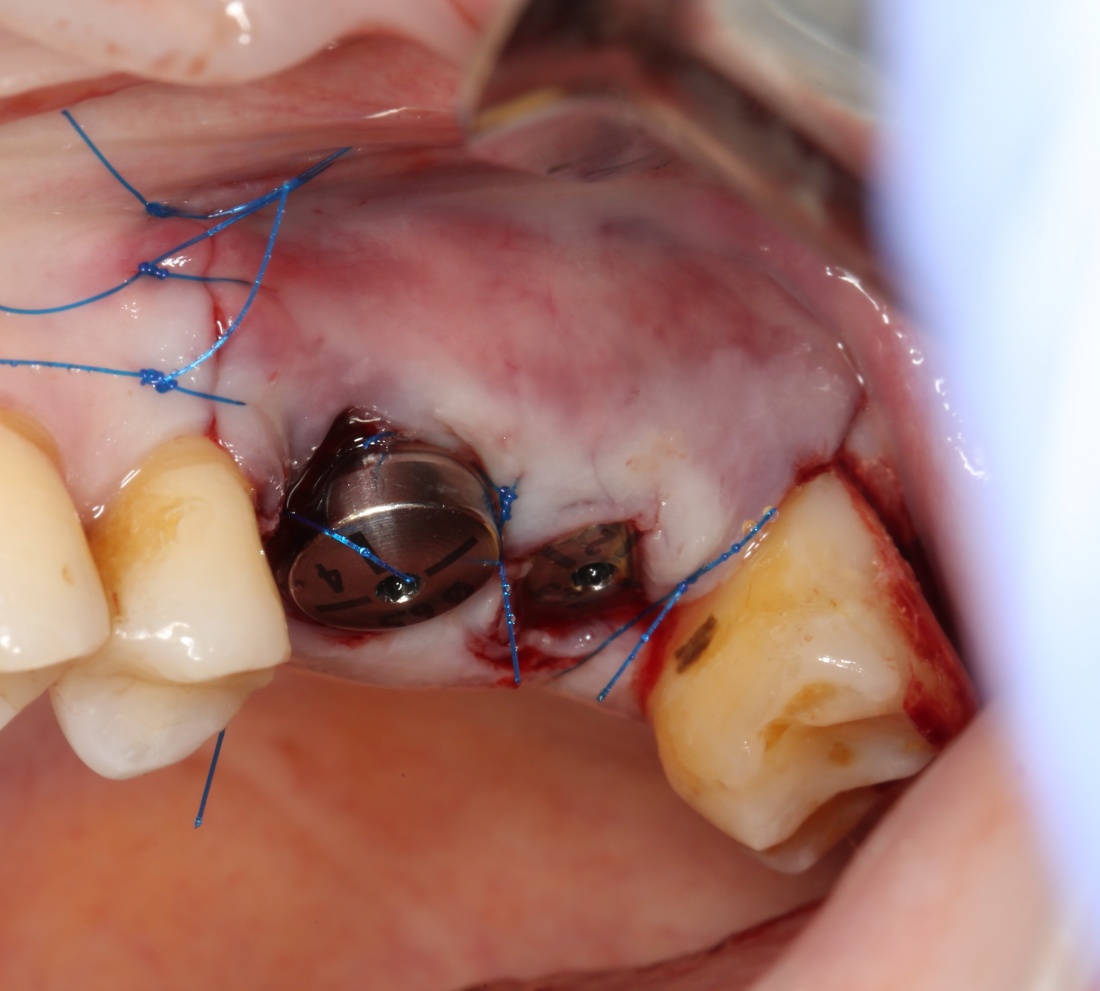

Простой синуслифтинг. Часть I.